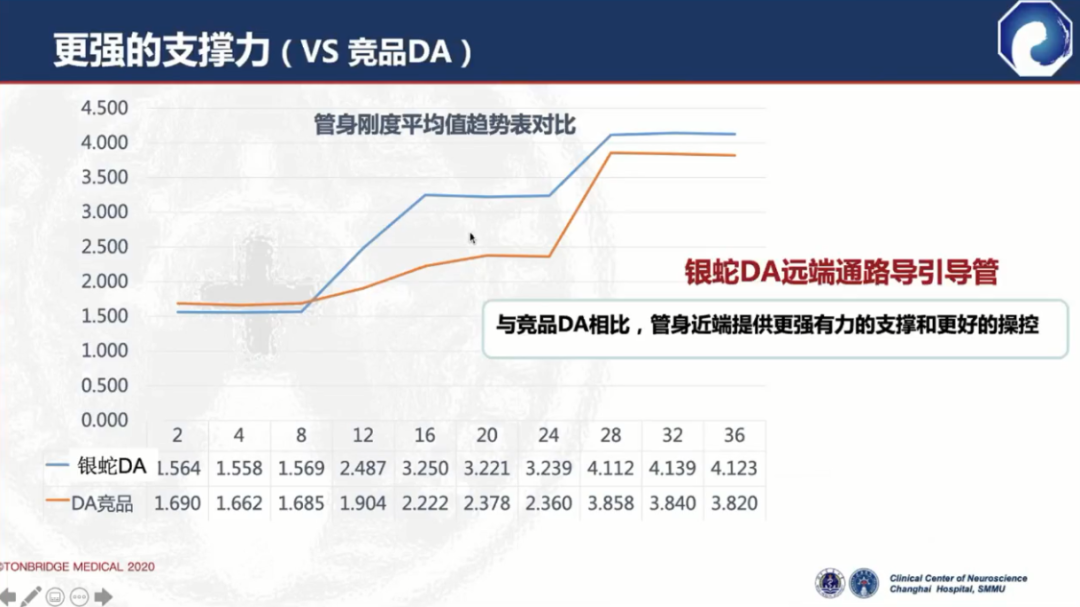

与竞品DA相比,弓部和近端支撑力更强